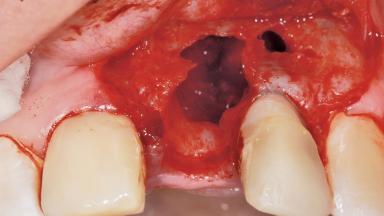

Late Placement of an Implant in a Maxillary Left Central Incisor Site

A 36-year-old female patient was referred for the replacement of the upper left central incisor (tooth 21), which had fractured. Although the tooth had been asymptomatic for many years, the crown began to loosen, at which time she presented to her dentist for an assessment. Teeth 21 and 22 had both been endodontically treated many years previously. She was a healthy individual and a non-smoker.

Bone Augmentation Horizontal|Staged

Augmentation Materials Xenogenous|Membrane

Bone Volume Horizontally and vertically sufficient Horizontally deficient Deficient vertically or deficient vertically AND horizontally

Bone Volume Deficient horizontally, requiring prior grafting